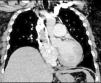

Inicialmente, se considera que cursaba con angioedema por lo que se inicia manejo con antihistamínico y corticoide, oxígeno suplementario, con lo cual se obtiene mejoría parcial, por lo que se establece como diagnóstico diferencial del síndrome de la vena cava superior. Entre los hallazgos positivos se encontró hipercapnia (PcO21 37,4mm Hg), gradiente alvéolo arterial aumentado (50,7), poliglobulia (Hb2 20,6, HCto3 65%) y LDH4 elevada (460). En la tomografía del cuello se descartan masas, se complementa el estudio con la angiotomografía del tórax, la cual evidencia un gran trombo oclusivo que compromete la vena cava superior, con extensión a su desembocadura en la aurícula derecha, tromboembolia pulmonar con compromiso segmentario en el lóbulo inferior izquierdo asociado a consolidaciones parenquimatosas, probablemente, por infartos pulmonares, probable hipertensión pulmonar precapilar y dilatación tanto auricular como ventricular derecha (figs. 1 y 2).